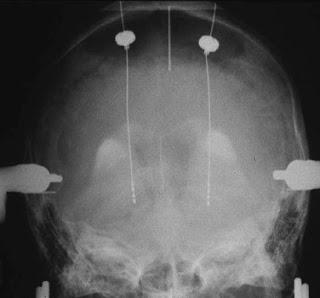

Traitement chirurgical de la maladie de Parkinson: électrodes de stimulation implantées dans les noyaux subthalamiques. In Médecine Nucléaire Volume 31, Issue 6, June 2007, Pages 304 - 313

Source iconographique et légendaire: http://www.sciencedirect.com/science/article/pii/S0928125807001295